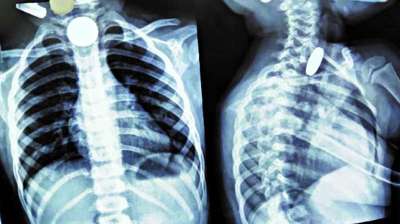

बच्चे ने मुंह में डाले सिक्के, सांस अटकने लगी; मेडिकल टीम की सतर्कता से टली बड़ी अनहोनी

दिल्ली : दिल्ली के एक सरकारी अस्पताल के डॉक्टरों ने 12 वर्षीय बच्चे की जान बचाई है। बच्चे ने पांच और दस रुपये के तीन सिक्के निगल लिए थे। सिक्के...